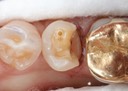

Kyle Chock #2 pre-op

Kyle Chock #2 caries removal

Kyle Chock #2 prep